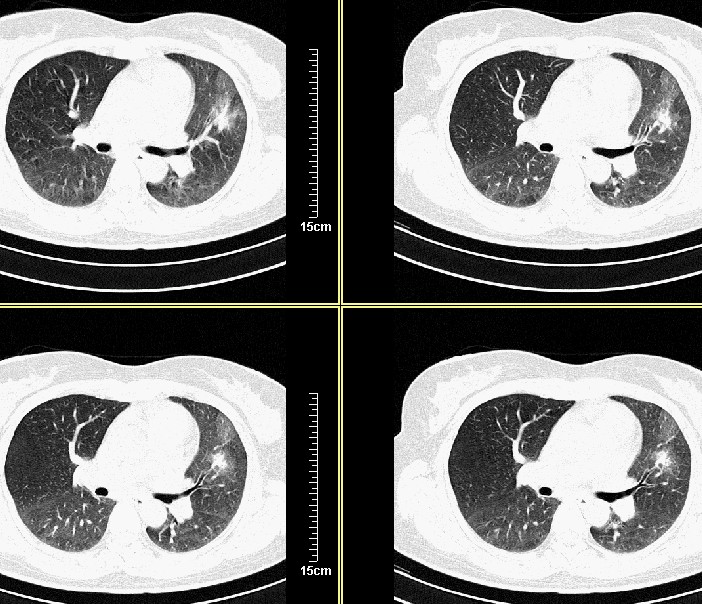

标题: CT8248B:女45岁,三天后复查,经支气管镜注药,会不会是肺 [打印本页]

标题: CT8248B:女45岁,三天后复查,经支气管镜注药,会不会是肺

应该能确定是恶性病变,三天前周围出现的淡薄景应该是肺泡内积血

3天后复查:病变明显好转、吸收:考虑炎症可能性大

支气管注药后3天后复查:病变明显好转、吸收:考虑炎症可能性大.

3天后复查:病变明显好转、吸收:考虑炎症可能性大.肿瘤待排

病灶似乎呈片样,密度不均匀,3天后复查:病变明显好转、吸收:考虑炎症可能性大 。

气管注药后3天后复查:病变明显好转、吸收:考虑炎症可能性大,肺癌待排!